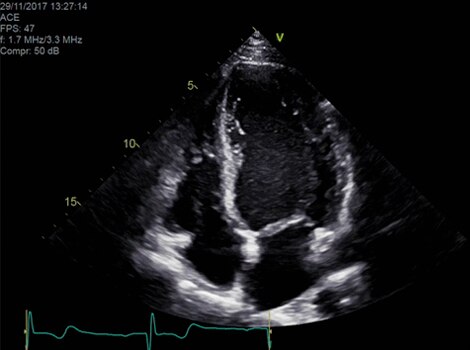

VividTM Family Cardiac Ultrasound Automated Function Imaging (AFI)

Assess left ventricular function and cardiac performance with clarity, improving clinical confidence. Read More

Vivid Family Cardiac Ultrasound

Vivid E95 with cSound performance makes 4D as easy as 2D to quantify left ventricular wall motion. Read More

Vivid™ Family Cardiac Ultrasound with Automated Quantification

Assess left ventricular function and cardiac performance with clarty,improving clinical confidence.Read More